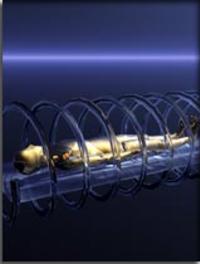

L’hypertension artérielle pulmonaire (HTAP) chronique d’origine thromboembolique est caractérisée par l’obstruction des vaisseaux pulmonaires [...]

L’utilisation d’oxygénateurs extracorporels à membrane, communément appelés ECMO (pour ExtraCorporeal Membrane Oxygenation) se développe [...]